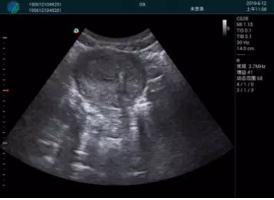

清晰顯示孕囊,通過軟件包計(jì)算孕齡7w+6d

M20實(shí)時(shí)引導(dǎo),術(shù)中清晰顯示孕囊被破壞和抽吸針的過程,清晰顯示吸引針

抽吸結(jié)束后縱切子宮,孕囊已被完全抽吸,未見明顯殘留